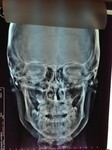

Paziente candidato a intervento di chirurgia Ortognatica